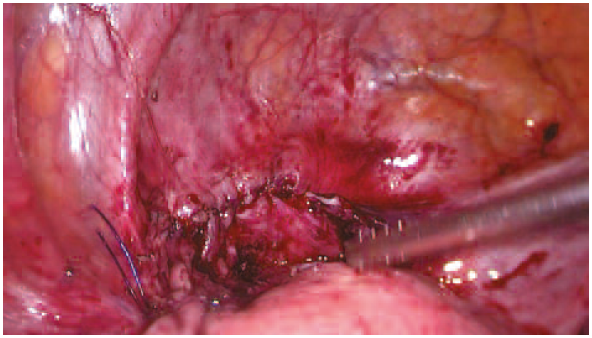

При осмотре спаечный процесс в брюшной полости не выражен, однако в области свища визуализировалось выраженное воспаление. Рассекли брюшину в области пузырно-маточной складки, дальнейшее выделение производили тупым и острым путем при помощи ультразвукового диссектора и хирургического аспиратора-ирригатора (рис. 2). В процессе разделения вскрыт МП в области свища и вскрыта матка в области передней стенки. Дефект стенки матки ушит двумя рядами швов непрерывным швом нитью «Стратофикс» 3-0 (рис. 3). МП осмотрен со стороны слизистой, иной локализации свища не выявлено. Произведено ушивание стенки МП двухрядным непрерывным швом нитью «Стратофикс» 3-0 (рис. 4, 5). Осуществлен контроль гемостаза, снят карбоксиперитонеум, удалены рабочие и оптический троакары, ушит дефект в области пупочного кольца, швы на кожные раны. Дренирование МП осуществлялось уретральным катетером Фолея №20. В послеоперационном периоде проводили профилактику тромбоэмболических осложнений, обезболивание парентеральными анальгетиками.

Рис. 2. Воспалительные ткани в области свища.

Fig. 2. Inflammatory tissue in the fistula area.